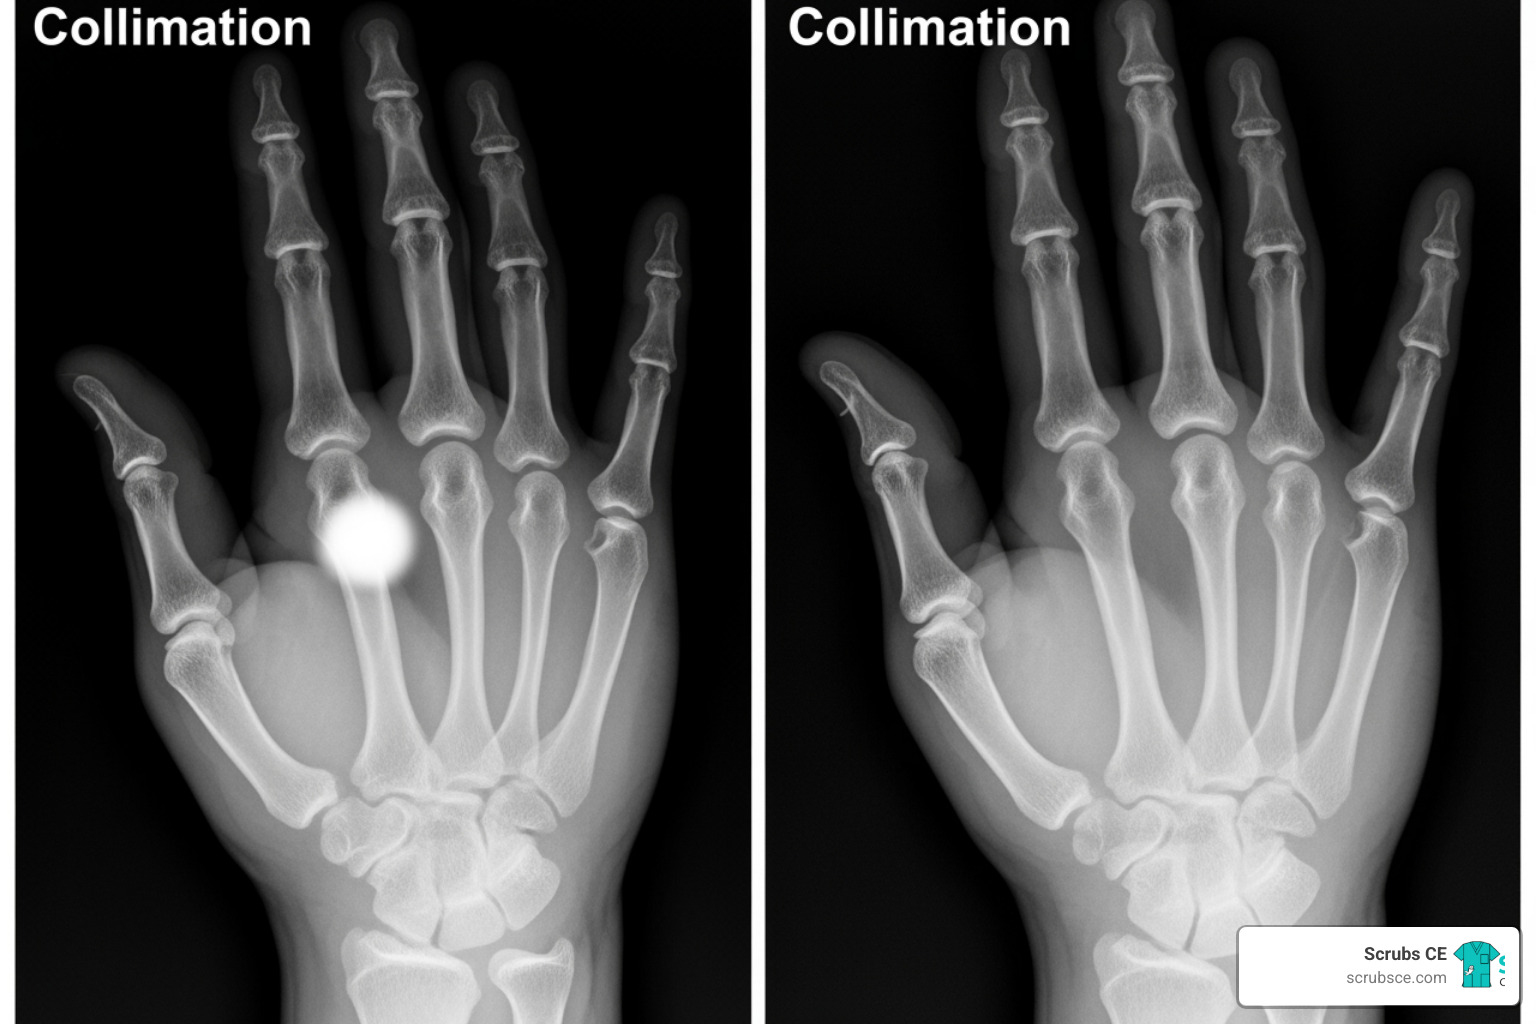

Physical collimation—restricting the X-ray beam to the area of interest—is a fundamental skill with a powerful impact. Proper collimation reduces patient dose and improves image quality by minimizing scatter radiation, which degrades contrast and detail.

It is crucial not to confuse this with electronic masking (or shuttering). This post-processing tool digitally crops an image to make it look properly collimated, but it does nothing to reduce the patient’s radiation dose or prevent the scatter that already occurred. Real collimation happens before the exposure. For examples, see Collimate to improve image quality.